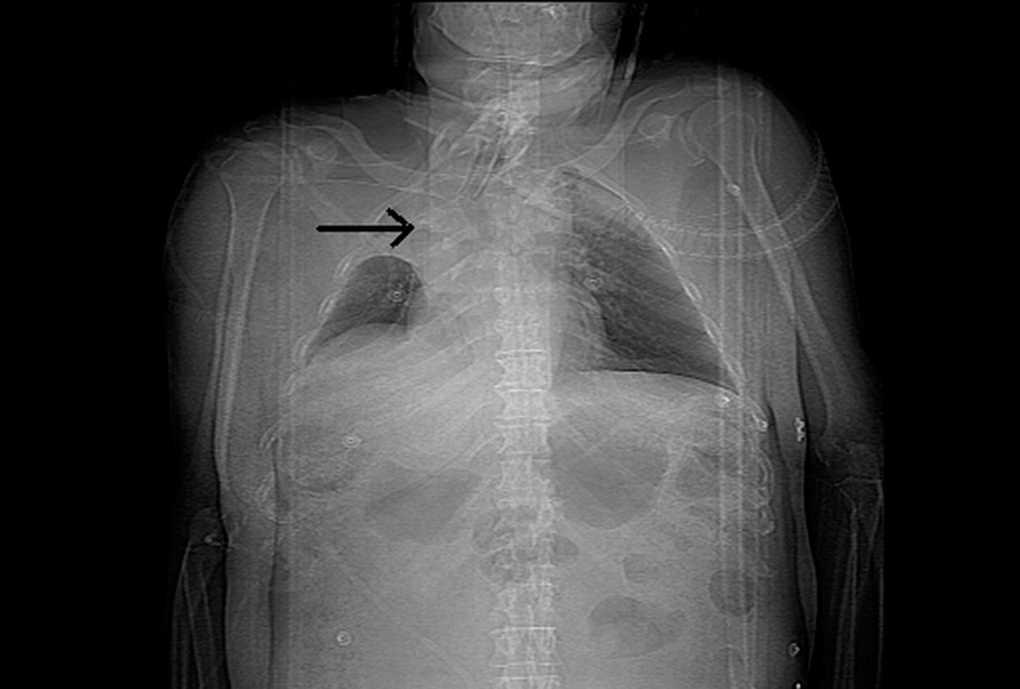

Paciente de 45 años de edad, sin antecedentes médicos de interés, que es remitido a la Unidad de Cuidados Intensivos tras sufrir accidente de tráfico. En la exploración física se aprecia hipoventilación en hemitórax derecho. Ingresa intubado y conectado a ventilación mecánica. Se realiza radiografía de tórax donde se evidencia una atelectasia del hemitórax derecho en el contexto de un traumatismo torácico con existencia de dos cuerpos extraños de densidad radioopaca (fig. 1). Debido a persistencia de alteraciones en la gasometría pese a ventiloterapia, se realizó tomografía computarizada (TC) pulmonar urgente hallándose dos piezas dentarias a nivel endobronquial (fig. 2, reconstrucción coronal). Posteriormente se procedió a extracción de las mismas mediante broncoscopia. Se trataba de una atelectasia postraumática por impactación de dos piezas dentarias a nivel endobronquial.

Figura 1